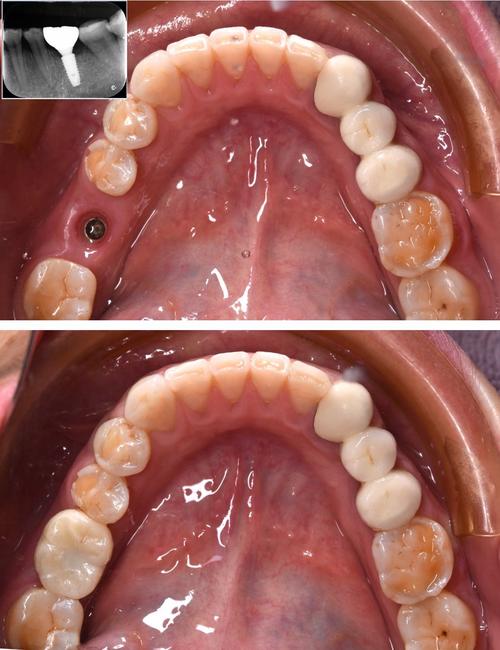

- 种植体(人工牙根): 植入牙槽骨内的部分,替代天然牙根,它没有神经和血管,没有感觉。

- 牙冠: 露在口腔内的部分,通常由陶瓷(如氧化锆)或烤瓷材料制成,模拟牙齿的外观和功能,它通过基台连接到种植体上。

- 种植体通过骨结合(Osseointegration)与牙槽骨直接长在一起,非常稳固,几乎没有动度(比真牙稳固得多)。

- 美观效果: 牙冠的颜色、形态、透明度可以高度模拟邻牙,达到以假乱真的美观效果。